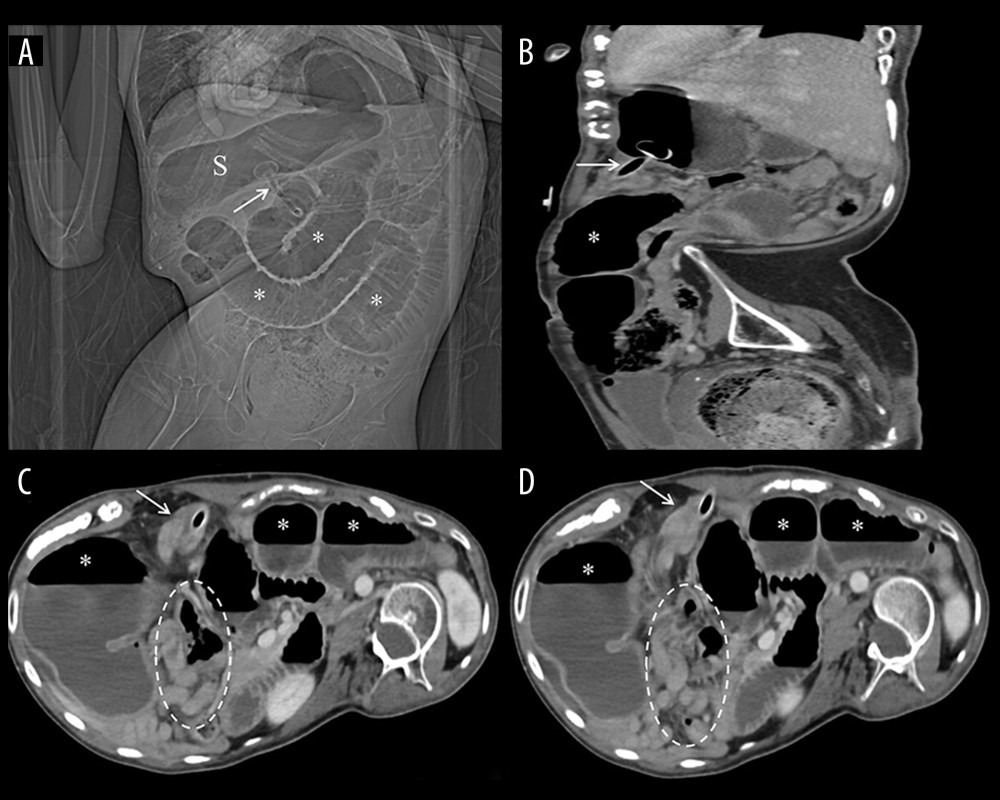

Jejunal Volvulus Around Gastrostomy Tube: An Exceptional

Jejunal Volvulus Around Gastrostomy Tube: An Exceptional. bowel loops distal to the tube (encircled). A case of small-bowel obstruction after insertion of a percutaneous endoscopic gastrostomy tube due to mesenteric , imageXml.php?i=amjcaserep-22- , imageXml.php?i=amjcaserep-22-. The Impact of Policy Management are bowel loops dilated after g tube placement and related matters.